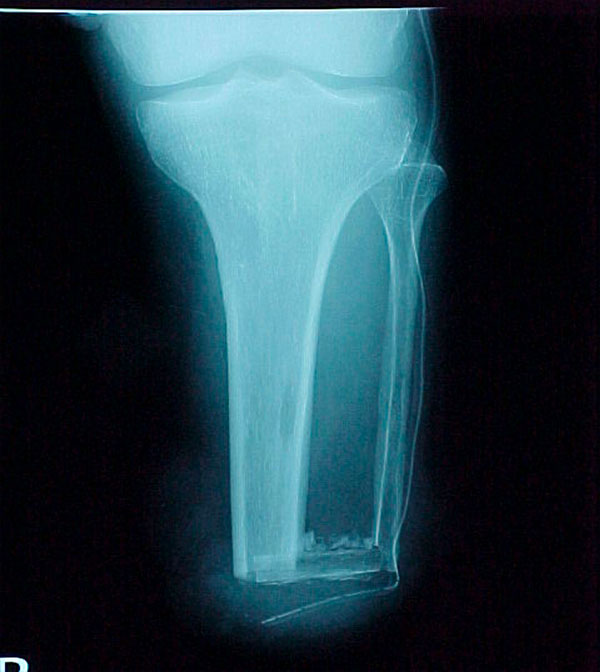

- Primary Objective RCT to evaluate the use of recombinant protein in patients at high risk for nonunion

- Focus Area Reconstructive Surgery & Non-Surgical Management to Improve Bone Healing

- Sponsor DoD PRORP

- Primary Objective To define a serum protein based diagnostic for the progression and failure of fracture healing, though the identification of a set of serum proteins that appear at early times of biological healing and show a specific correlation with later radiological and functional signs used to define delayed healing and non-union.